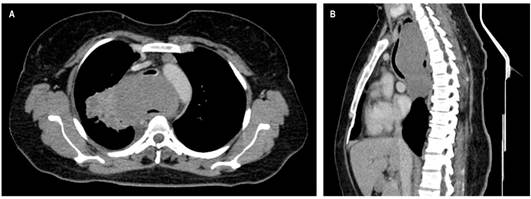

Se presenta el caso de una paciente femenina de 38 años con cuadro clínico consistente en disfagia de 1 año de evolución asociado con episodios ocasionales de hematemesis, por lo que se realizó una endoscopia de vías digestivas altas que evidenció una lesión endoluminal, friable e irregular que se localizó a 27 cm desde la arcada dentaria y de 12 cm de longitud, de la que se tomó una muestra para estudio histopatológico, que reportó una lesión benigna compatible con leiomioma. Sin embargo, se amplió el estudio con una TAC de tórax contrastada en la que se observó una masa tumoral a nivel del esófago cervical de 128 mm x 66 mm x 84 en diámetros L x AP x T, que se extiende hasta el esófago torácico transmural, exofítica, con realce homogéneo dependiente de la pared anterior la cual condiciona la obstrucción de la luz y ejerce un efecto de masa sobre la tráquea en un 70 % aproximadamente (Figura 1A y B).

Figura 1 TAC de tórax contrastado. Masa en el mediastino medio de 128 x 66 x 84 mm en diámetros L x AP x T, respectivamente, sin realce significativo posterior a la administración de medio de contraste, homogénea, de contornos parcialmente definidos lobulados, con extensión desde C7 hasta T7 con un efecto compresivo sobre las estructuras mediastinales adyacentes, en especial con la tráquea que desplaza el tejido en sentido anterior con disminución de su calibre sobre un 73 % aproximadamente; y en el esófago, donde se aprecia parcialmente su luz. Ganglios linfáticos subcentimétricos de localización prevascular, el de mayor tamaño con eje corto de 8 mm; a nivel paraaórtico se observan ganglios linfáticos con eje corto de 10 mm. A. Corte axial. B. Reconstrucción sagital.